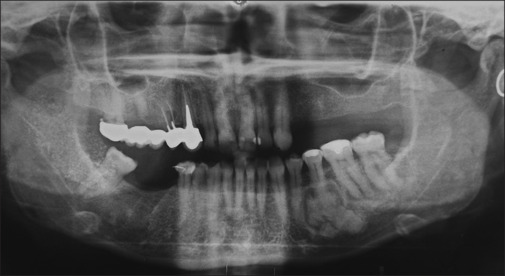

Fibrous dysplasia is a rare genetic syndrome that affects bone tissue. This pathology replaces the mineralized matrix of the bone affected with connective and fibrous tissue. This article describes a mandibular fibrous osseous dysplasia case and its surgical treatment. A 45-year-old woman complained about a slow development of swelling of the left mandibular bone. The orthopantomography (OPT) and the cone beam computed tomography (CBCT) revealed a well-circumscribed sclerotic lesion with a ground-glass appearance apical to the 3.5 element. The surgery was performed to excise the lesion. Anatomopathological examination of tissue confirmed the suspects among the diagnosis of fibrous dysplasia. The patient underwent to follow-up of 4 years, and no recurrences were found. In the absence of a univocal consensus on therapy, surgery remains the treatment of choice for unifocal forms.